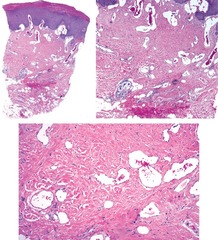

Liquefactive Necrosis

Front

Back